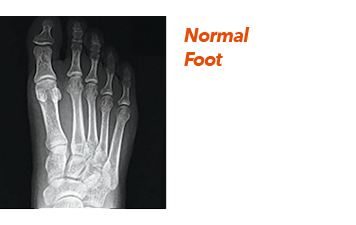

Bunions are due primarily to genetic factors, but can become painful over time due to trauma, ill-fitting shoes and poor foot structure. What happens, is that the bone connected to the big toe starts to drift outward pushing the big toe sideways into the other toes which can also lead to painful hammertoes, corns and calluses.